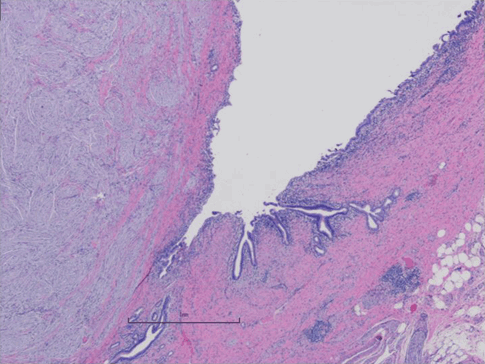

Given the clinical suspicion for distal cholangiocarcinoma without alternative means for a more definitive tissue diagnosis and no evidence of metastatic disease, surgical resection with appropriate lymph node harvest was offered as the next step in oncologic management. The patient consented to and underwent an open pancreaticoduodenectomy with resection of the gastric remnant. The operation was performed by a fellowship-trained specialist in both surgical oncology and hepatobiliary and pancreatic surgery. The prior gastrojejunal bypass anatomy was preserved, gastrointestinal continuity was restored with a Roux-en-Y pancreaticojejunostomy and choledochojejunostomy, and a feeding jejunostomy tube was placed in the common channel. Final pathology demonstrated proliferation of bland spindle cells compressing the distal common bile duct with the extension of some nerve fibers from the lesion in a tangled irregular pattern suggestive of a traumatic neuroma (Figure 3).

Figure 3. Final pathologic examination of the periductal mass associated with the biliary stricture, demonstrating a spindle pattern consistent with a bile duct neuroma without evidence of malignancy